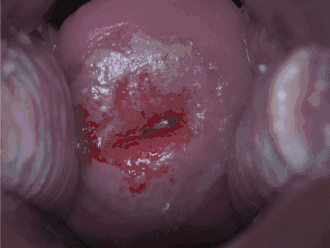

Dépistage

Les deux méthodes de dépistage disponibles sont le frottis cervical et le dépistage du VPH. La NCI est généralement découverte par un frottis. Le but de ce test est de détecter des changements potentiellement précancéreux grâce à un échantillonnage aléatoire de la zone de transformation. Les résultats du frottis peuvent être rapportés à l'aide du système Bethesda (voir ci-dessus). La sensibilité et la spécificité de ce test étaient variables dans une revue systématique portant sur l'exactitude du test. Un test de frottis anormal peut conduire à une recommandation de colposcopie du col de l'utérus, une procédure en cabinet au cours de laquelle le col de l'utérus est examiné sous grossissement à l'aide d'un microscope. Chaque zone d'apparence anormale fait l'objet d'un prélèvement/biopsie.[réf. nécessaire]

La colposcopie peut parfois être douloureuse chez certaines patientes. Certaines études suggèrent que l'injection d'un anesthésique local et d'un vasoconstricteur dans le col de l'utérus peut réduire la perte de sang et la douleur pendant la colposcopie[17].